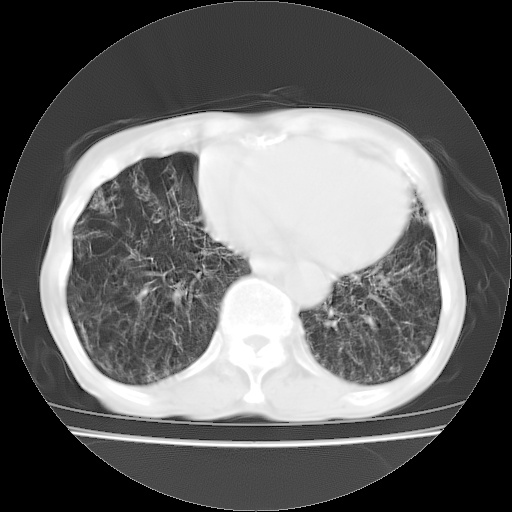

病人发热、气促就诊。原二周前已行ct扫描,当时诊断为双肺下叶、右肺中叶支气管扩张并感染,双肺上叶片状渗出性病变。今天复查胸部ct,双肺下叶支气管扩张并感染病灶较前明显吸收,但双肺上叶渗出性病变较范围较前明显增大。

现传今天ct图像给大家讨论。

双肺多发大片状、斑片状高密度渗出影,部分实变,考虑病毒性肺炎。